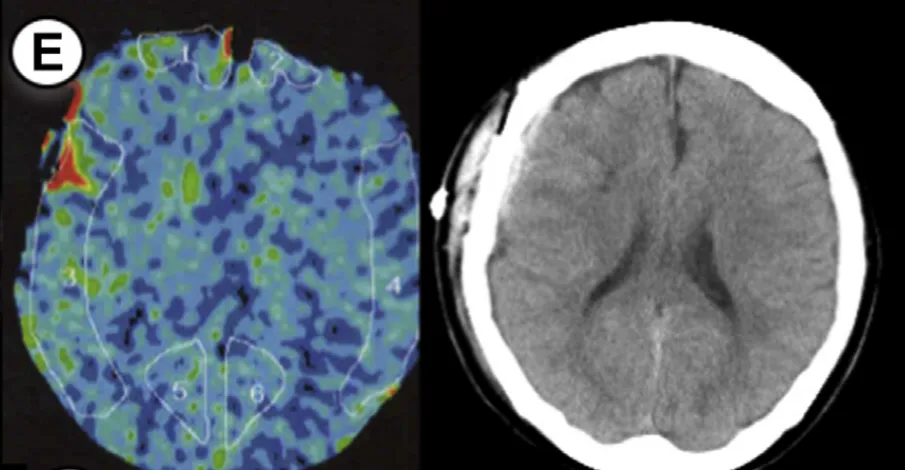

病例5

49岁男性,有TIA病史,行左侧大脑手术。方法1 rCBF增加率78%,方法2高达149%。术后第2天发现少量蛛网膜下腔出血,经1天镇静后出血未扩大。

7例病例年龄范围25-55岁,出血类型包括脑出血(ICH)、蛛网膜下腔出血(SAH)、硬膜下血肿(SDH)及混合出血,发病时间集中于术后1-5天。所有病例rCBF增加率均超过阈值,证实了预警系统的可靠性。

通过氙气增强CT,在大脑中动脉供血区固定部位测量rCBF,术后即时完成首次检测。